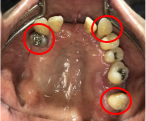

Before

赤丸は抜歯しました

After

【義歯を装着したところ】

【義歯を外したところ】

マグネット義歯

緑丸は組み込まれたマグネット